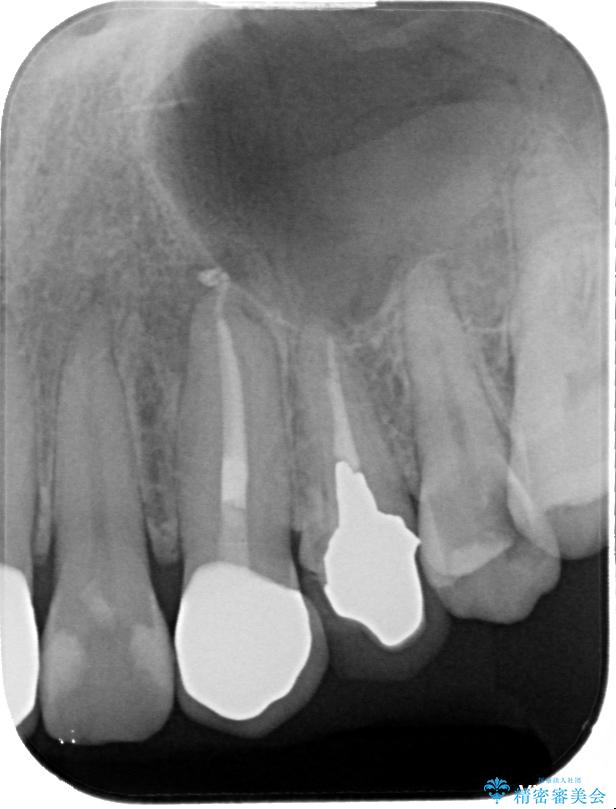

治療前

• 「抜歯してブリッジ」と言われた20代女性が選んだ治療とは|たった4か月で自然な笑顔に抜歯即時インプラント+審美補綴の症例 治療前画像

▶左上中切歯

土台を再度丁寧に整え、オールセラミッククラウンにて補綴

▶左上犬歯

根管治療行い感染除去した後、最終補綴はオールセラミッククラウンにて審美的に